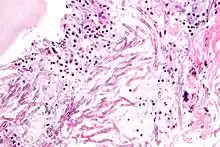

| Micrograph showing a mycosis (aspergillosis). The Aspergillus (which is spaghetti-like) is seen in the center and surrounded by inflammatory cells and necrotic debris. H&E stain. | |